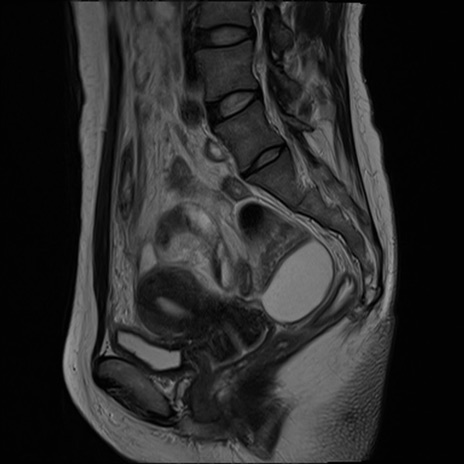

症例39 T2WI(矢状断像)

MRI(4日後)